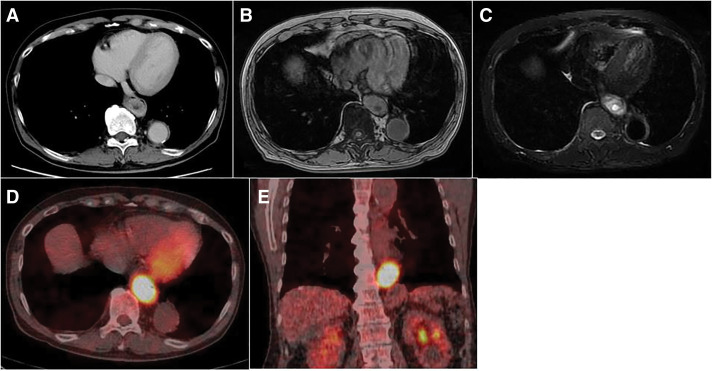

Case presentation: A 77-year-old man presented with epigastric pain. Upper gastrointestinal endoscopy revealed an esophageal mass, prompting referral to our hospital. Endoscopic ultrasonography (EUS) identified a hypoechoic submucosal tumor with multiple cystic components in the lower esophagus. However, EUS-guided fine-needle aspiration (EUS-FNA) did not yield a definitive diagnosis. CT scan demonstrated a 60-mm space-occupying lesion (SOL) in the lower thoracic esophagus with peripheral contrast enhancement and a central low-density area. MRI revealed a SOL in the lower esophagus with high signal intensity on T2-weighted images and moderate signal intensity on T1-weighted images. The lesion contained cystic components exhibiting high T2 and low T1 signal intensities. FDG-PET/CT revealed intense FDG uptake, increasing from maximum standardized uptake value (SUVmax) 11 to 18 over time. Given the large size of the tumor, symptomatology, and inability to exclude malignancy-particularly high-risk gastrointestinal stromal tumor-surgical resection was performed. Laparoscopic esophagectomy was conducted using intraoperative endoscopy for tumor identification. The esophagus was transected proximally using a linear stapler, followed by extracorporeal gastric conduit reconstruction and the overlap technique was used to perform an esophagogastric anastomosis. Postoperatively, anastomotic leakage was detected on day 3, requiring emergency reoperation. The leak had resolved by POD 26, and the patient was discharged on day 48 after the second surgery (day 51 after the initial surgery). Histopathological examination revealed multiple cysts of varying sizes within the lamina propria, lined by columnar epithelium, with no evidence of malignancy. The final diagnosis was esophageal retention cyst.